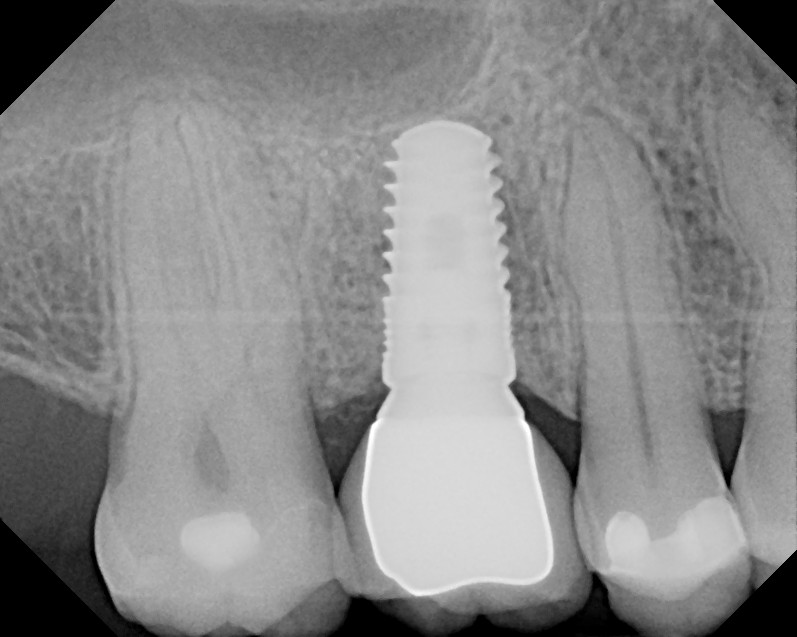

Stomatologiyanın təməl vəzifələrindən biri, itirilmiş dişlərin funksiya və estetik olaraq təbiiyə ən yaxın şəkildə bərpa edə bilməkdir. Dişsizliyin estetik və funksional olaraq yüksək səviyyədə reabilitasiyası, pasiyentlərin çeynəmə, danışma və gülmə kimi funksiyalarını qüsursuz icra edə bilməsi baxımından çox önəmlidir. Diş implantları xüsusi texnologiya hazırlanaraq, itirilmiş dişin bərpası üçün tətbiq edilən süni diş kökləridir. Bu metod təbiiyə ən yaxın bərpanı vəd edən müalicə metodu kimi uzun illərdən bəri beynəlxalq miqyasda geniş tətbiq olunur. İmplantasiya, bu işin peşəkarı yüksək ixtisaslı mütəxəssis tərəfindən qısa bir müddət davam edən prosedur vasitəsilə ağrısız, qısa müddətə və həyati funksiyaların məhdudlaşmaması şərti ilə həyata keçirilən müalicə üsuludur.

Dental implantlar əsasən titandan hazırlanır. Bu materialdan hazırlanmasının ən başlıca səbəbləri, bu metalın orqanizm tərəfindən rədd edilməməsi, heç bir allergik reaksiyaya səbəb olmaması və bu təyinat üçün yetərli möhkəmliyinin olmasıdır. Diş implantları vasitəsilə, tək diş əksikliyindən, çoxsaylı diş əksikliyi və tam dişsizlik halları funksional və estetik bərpa edilə bilir. İmplantın üzərinə hazırlanan diş konstruksiyaları müvafiq vəziyyətlərdə implantların tətbiqi ilə eyni gündə və ya müəyyən bir sağalma dövrünün keçməsindən sonra hazırlana bilir. İmplantların istismar müddəti, doğru planlama və icraat həyata keçirildiyində, eyni zamanda yetərli gigiyenik qulluq şəraitində bir neçə on illik bir periyodu əhatə edə bilir.